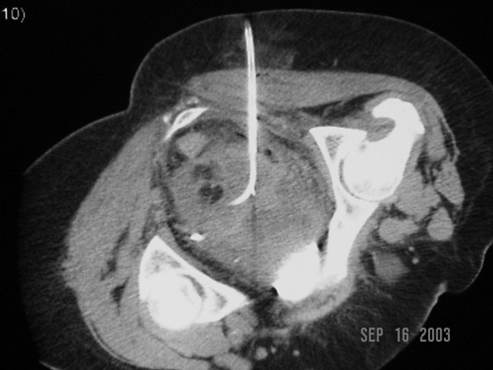

The top-row images belong to a middle-aged woman with skin metastasis from small cell lung cancer who developed a deep pelvic abscess. The first image shows planning of transgluteal drainage of the collection, while the second image captures the final position of a 12F pigtail catheter deployed into it.